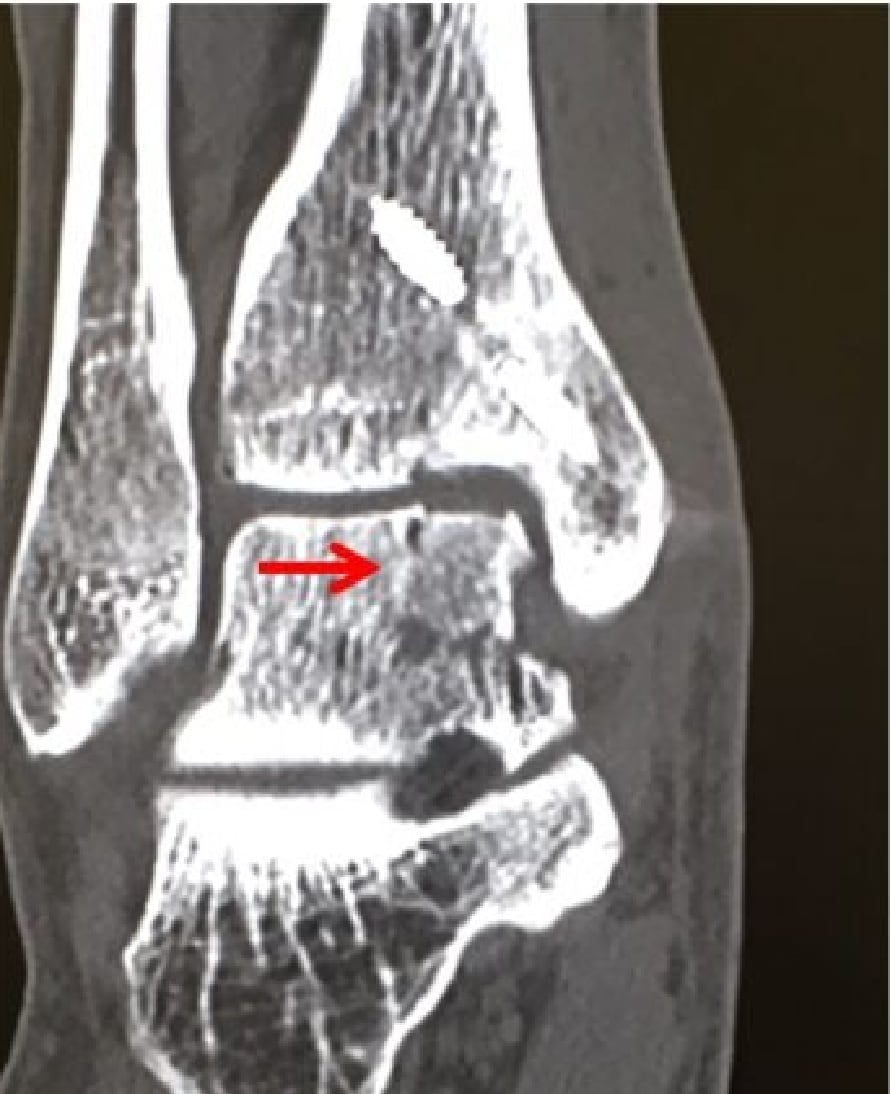

骨軟骨柱移植前

骨軟骨柱移植後

術後6ヶ月経過CT 1

術後6ヶ月経過CT 2

骨軟骨柱移植術後CT